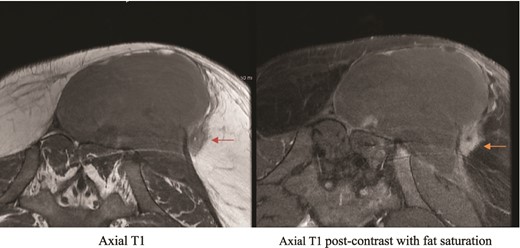

MRI showing suspicious lesion. Postoperative MRI images show re-demonstration of suspicious lesion when correlated to prior MRI from private hospital. The lesion shows low T1 signal intensity (orange arrow), and post-contrast enhancement with central linear area of non-enhancement.